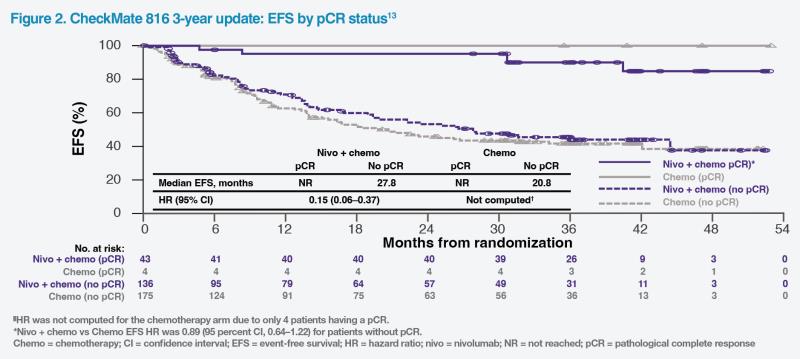

CheckMate 816 investigators noted the strong association between pCR and clinical benefit and suggested that pCR may be used as an early indicator of therapeutic efficacy in resectable NSCLC.4 In the 3-year update of CheckMate 816, among patients with a pCR, median event-free survival (EFS) was not reached in both treatment groups. In patients without a pCR, median EFS was 27.8 months in the nivolumab group vs 20.8 months with chemotherapy alone (HR, 0.89; 95 percent CI, 0.64–1.22). (Figure 2) Similar results were observed in terms of overall survival (OS). These results show that pCR was associated with both improved EFS and OS in patients treated with neoadjuvant nivolumab plus chemotherapy as well as those treated with chemotherapy alone.13